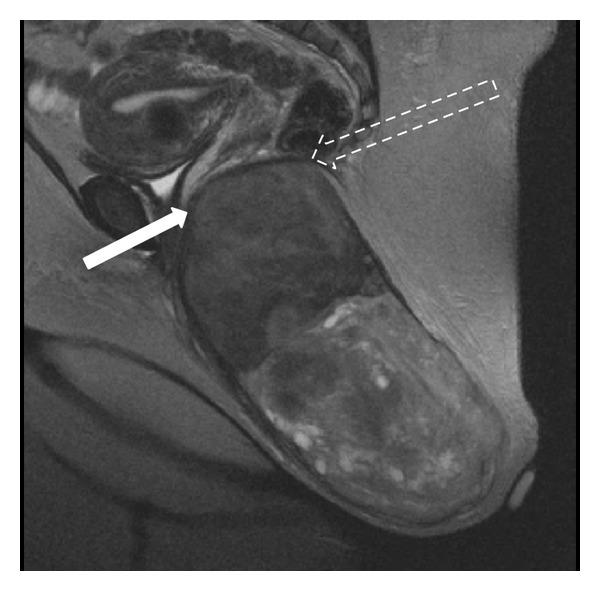

We report the case of a 40-year-old woman who presented with a large perineal mass with no rectal or vaginal involvement. Imaging could not rule out malignancy. She underwent wide surgical excision. Histological analysis revealed a large atypical leiomyoma, measuring 24 × 12 × 8 cm. Followup after two years showed no recurrence and she has been asymptomatic since surgery. This is the largest perineal leiomyoma reported so far.

我们报告了一例40岁女性病例,该患者会阴出现一个较大肿物,未累及直肠或阴道。影像学检查无法排除恶性肿瘤。她接受了广泛的手术切除。组织学分析显示为一个巨大的非典型平滑肌瘤,大小为24×12×8厘米。两年后的随访显示无复发,自手术以来她一直无症状。这是迄今为止报道的最大的会阴平滑肌瘤。